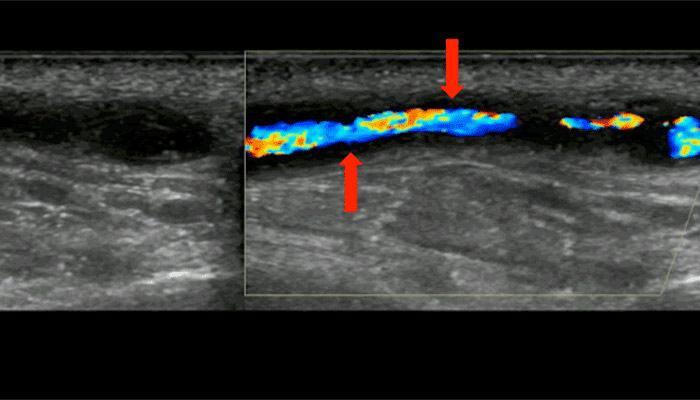

Ultrasound view, along the length of a branch of the temporal artery. The blood flowing in the artery is colored; the dark area on both sides (see arrows) is caused by swelling the wall of the artery, due to giant cell arteritis.